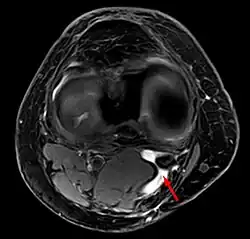

![]() Torbiel Bakera - Rezonans magnetyczny w płaszczyźnie osiowej | |

Torbiel Bakera (zwana także cystą Bakera lub torbielą dołu podkolanowego, pot. woda w kolanie) – nagromadzenie płynu w dole podkolanowym wskutek obrzęku i nagromadzenia się płynu w kaletce mięśnia półbłoniastego lub też wskutek przedostania się ku tyłowi płynu stawowego ze stawu kolanowego wskutek uszkodzenia torebki stawowej stawu kolanowego. Nazwana od chirurga Williama Morranta Bakera[1].